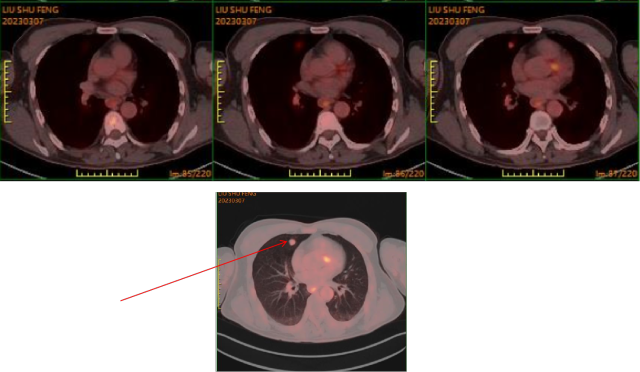

2. 随访:术后规律复查,2023-03-07:PET/CT(全身检查)诊断意见:1. 左肾肿瘤切除术后;左侧锁骨术后;2. 双肺多发结节,部分结节FDG代谢增高,考虑转移瘤;——肺转移。

2023-03-07 PET/CT: